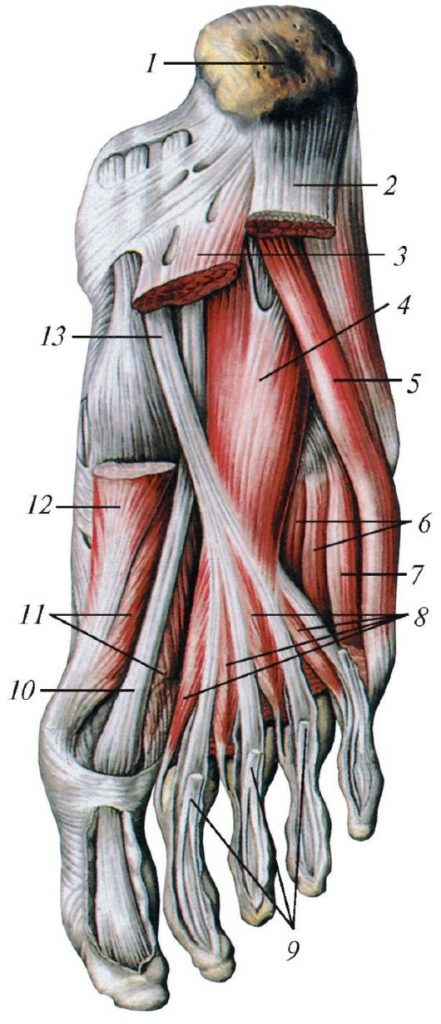

Анатомия подошвенной мышцы голени: подробное рассмотрение